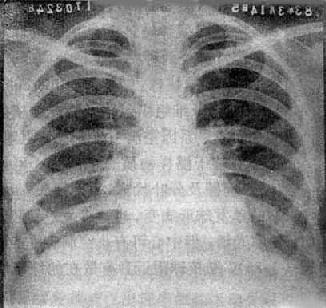

(1)一侧性肺不张:X线现为患侧肺野均匀致密,纵隔向患侧移位,肋间隙变窄(图3-1-7)。健侧肺可有代偿性肺气肿。

图3-1-7 一侧性肺不张

左侧支气管阻塞引起左侧全肺不张,显示左侧肺野均匀致密,

纵隔向患侧移位,肋间隙变窄,膈升高